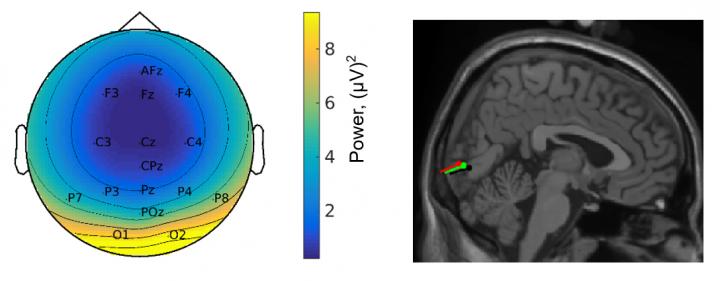

When processing visual stimuli, however, it makes a difference whether the person is sitting or moving: When walking around, the peripheral part of the visual field shows enhanced processing compared to the central part. This can be proven both by the behaviorally measured perception of the test persons and by their brain response.

This shift in visual preference makes sense. "It is above all the peripheral visual input that provides information about the direction and speed of our movement and thus plays an important role for navigation," says Dr. Barbara Händel. The neuroscientist from Julius-Maximilians-Universität (JMU) Würzburg in Bavaria, Germany, and her colleague Dr. Liyu Cao have published their findings in PLOS Biology .